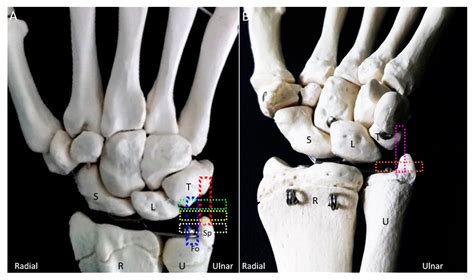

The Styloid Process Ulna is a bony projection located at the distal end of the ulna, one of the two bones in the forearm. It is situated on the medial side of the wrist, opposite the styloid process of the radius. This process serves as an attachment site for several ligaments and tendons, which are essential for the stability and movement of the wrist joint.

• The triangular fibrocartilage complex (TFCC), which stabilizes the distal radioulnar joint and helps distribute forces across the wrist.

• The ulnar collateral ligament, which provides medial stability to the wrist.

• The flexor carpi ulnaris tendon, which aids in wrist flexion and ulnar deviation.

By serving as an anchor for these structures, the Styloid Process Ulna contributes to the overall stability and functionality of the wrist and hand.